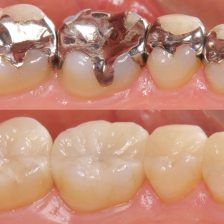

メタルフリー治療